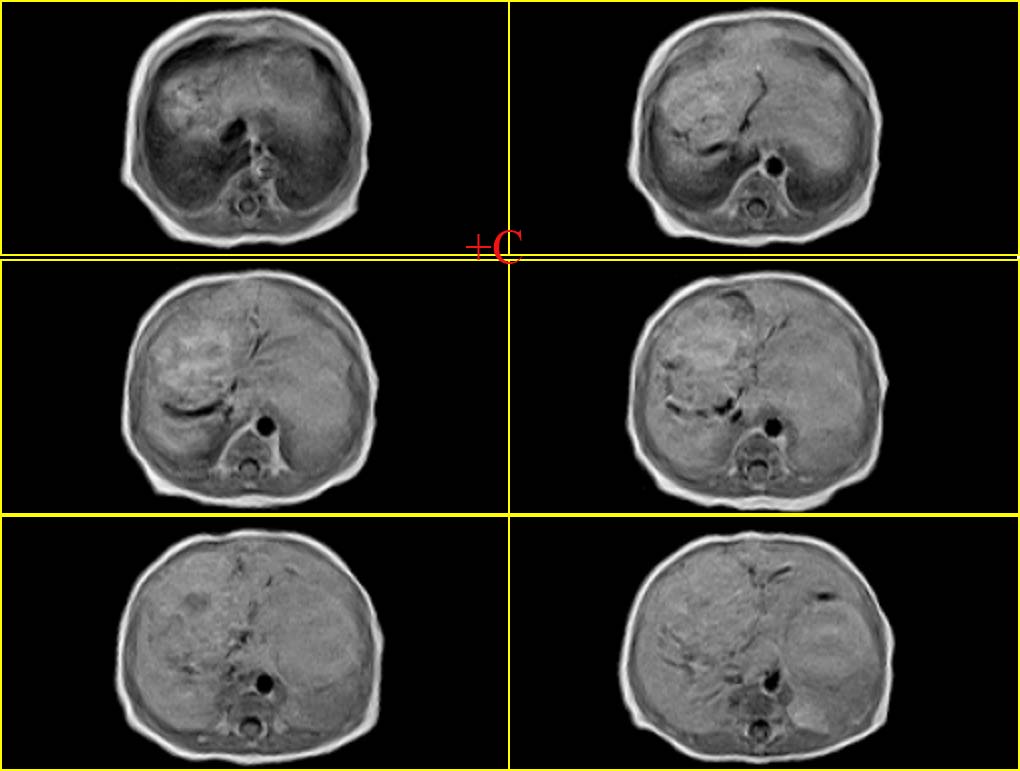

患者男性,3天.

因生育前b超发现肝脏占位,怀疑血管瘤而行mr检查.

血管内皮瘤,建议补充临床资料,如血常规,尤其血小板情况,有无充血性心衰,主要与肝母鉴别.